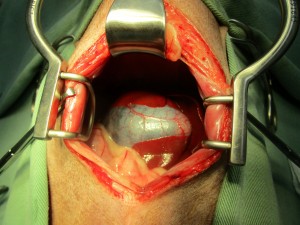

肝臓の間にはまっている胆嚢を丁寧に剥離し、2重結紮し切離しました。

摘出した胆嚢組織は内部がゼリー状に変性を起こしており、胆汁が正常に消化管へ流れていないことが予想されました。

病理組織検査:胆嚢粘液嚢腫、肝細胞変性